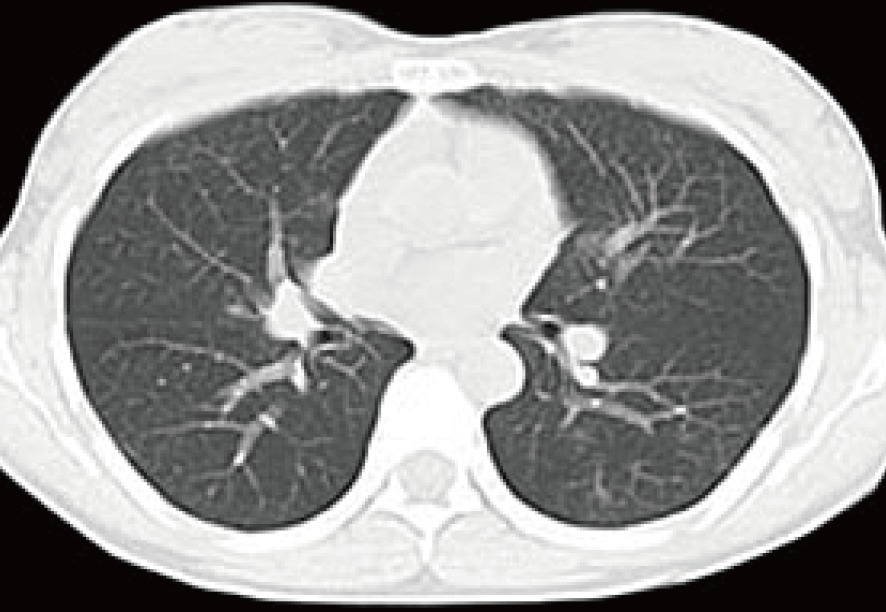

その6カ月後、頻繁な咳が出現しはじめ、主治医の判断で胸部CT検査を実施。結果は「乳癌の両肺転移、ステージ4」であった。即座に再入院、数クールにわたる抗がん剤の点滴治療が行われた。

治療前CTでは両肺に発生した転移がん病巣を認める(赤で囲まれた箇所)。

治療開始8カ月後、両肺に広がる転移性がんは概ね消失。引き続き治療継続と経過観察を指示した。